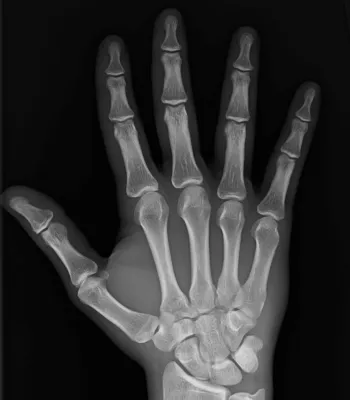

Radiographie de la main

Passer une radiographie de la main, du poignet ou du doigt

Vos centres d'imagerie médicale Lodi, La Rose et de Fuveau vous proposent de passer une radiographie de la main, du poignet ou du doigt.Les clichés radiographiques sont réalisés dans vos centres d'imagerie médicale en cas de douleur ou de traumatisme. Les radiographies  permettent de détecter les ...